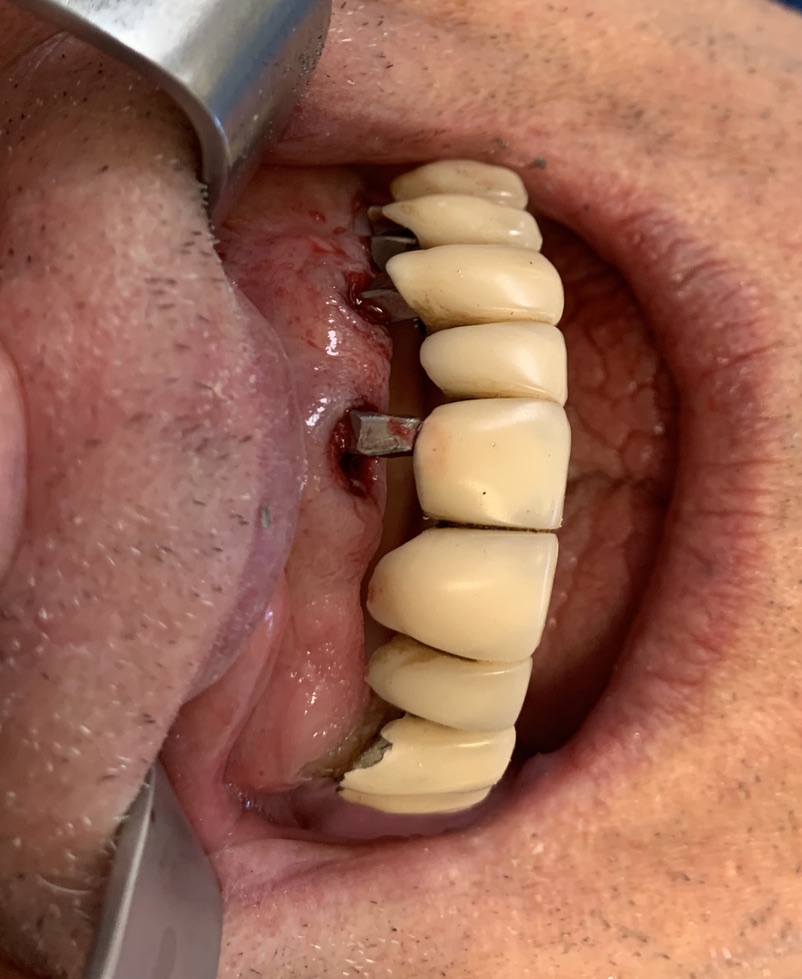

Implant type: Tramonte     No. Implants inserted: 2       Welding: No      Dental area: 21   23

Occlusal load: immediate     Complications: none      Video or written statement of satisfaction: video su Iophone xs.

O- the surgical maneuvers are so little invasive and so gentle as to make Tramonte implants indicated in old age, in smokers, in chronic diseases

P- Healing is fast

Q- normal chewing activity is immediately restored,